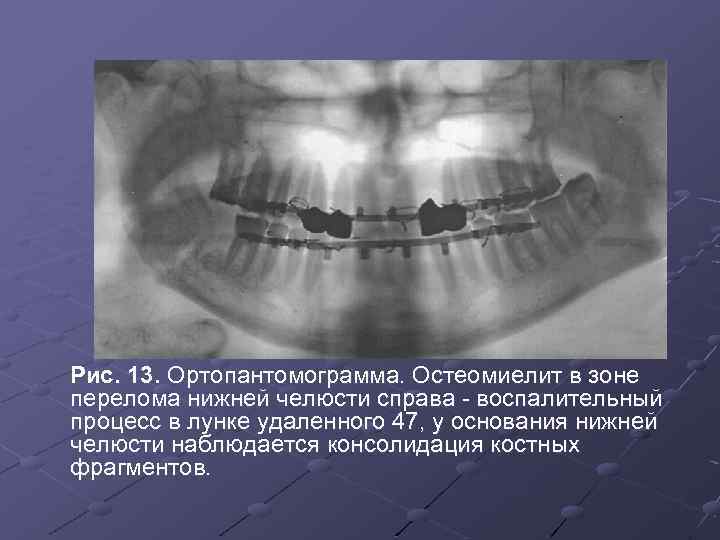

Рентгеновские снимки посттравматического остеомиелита челюсти: Медицинские случаи